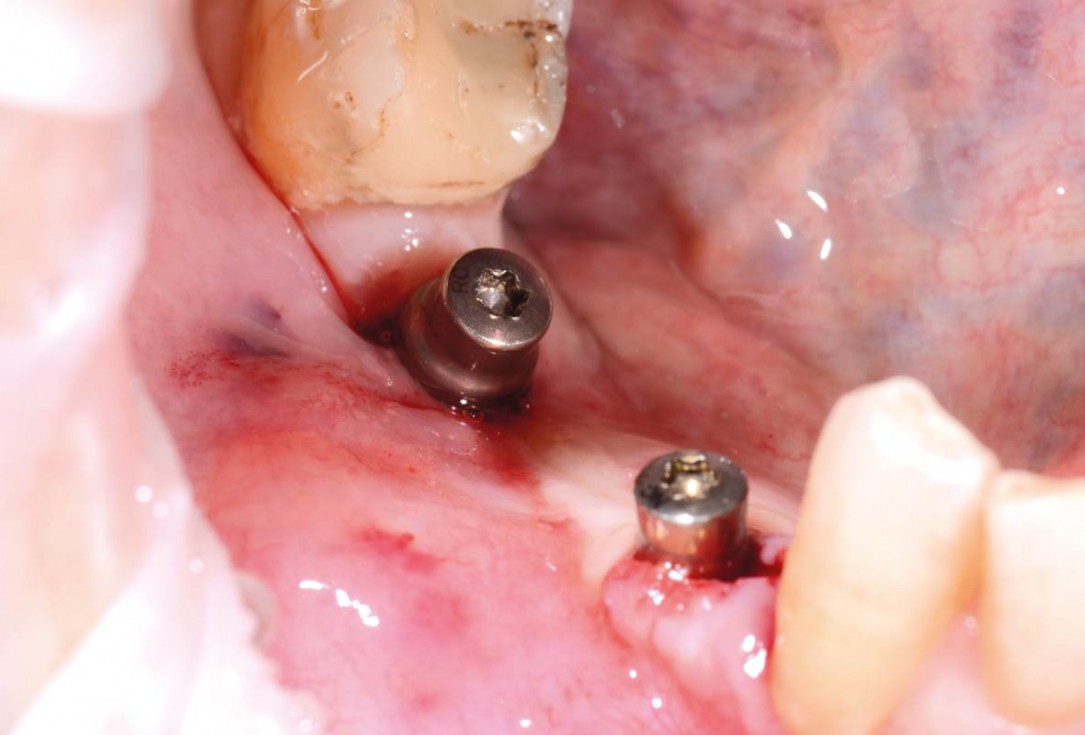

22/29 - Clinical view after insertion of the healing abutmentVertical bone augmentation and broadening of attached gingiva using cerabone®, permamem® and mucoderm® - Dr. R. Naimoli